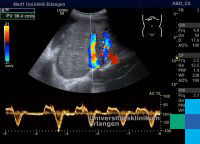

Die Stauungsleber ist eine durch eine Blutstauung hervorgerufene Krankheit der Leber. Grund für den verminderten venösen Blutabfluss aus der Leber kann ein Hindernis (z. B. Tumor, Thrombose) zwischen Leber und rechter Herzhälfte sein. Auch kann das Herz selbst die Ursache für den Rückstau sein (zum Beispiel ein Panzerherz, Pericarditis constrictiva).